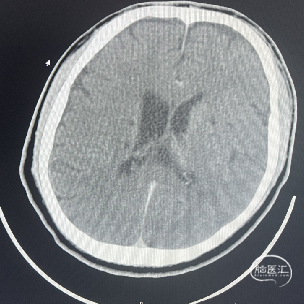

辅助检查:CT见右侧基底节区及右顶叶低密度病灶。

术后CT:术后即刻CT,以及术后24h CT。